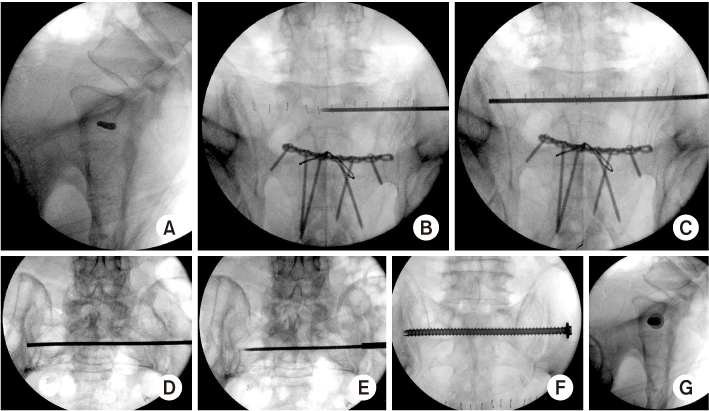

Fig. 4

(A–C) The trans-sacral trans-iliac screw should be placed transversely just below the ICD line. (D, E) The entry point was placed just anterior to the curve point. (F, G) The screw did not pierce the cortex around the sacral canal and foramen.